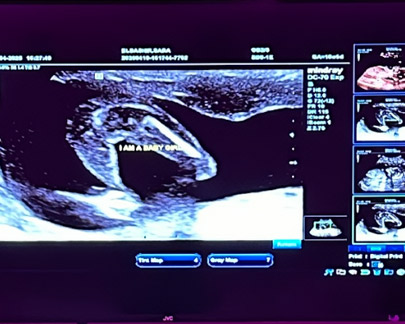

During the scan, a trained sonographer uses a handheld device called a transducer. This device is gently moved across the abdomen and sends sound waves into the body. When the waves return, the ultrasound system converts them into images that appear on a monitor.

The probe is then gently moved across the stomach while the ultrasound system displays real-time images on the monitor. Depending on the stage of development, movement, heartbeat and positioning may be visible during the scan.

Throughout the appointment, the sonographer will explain what can be seen on the screen and answer any questions you may have.